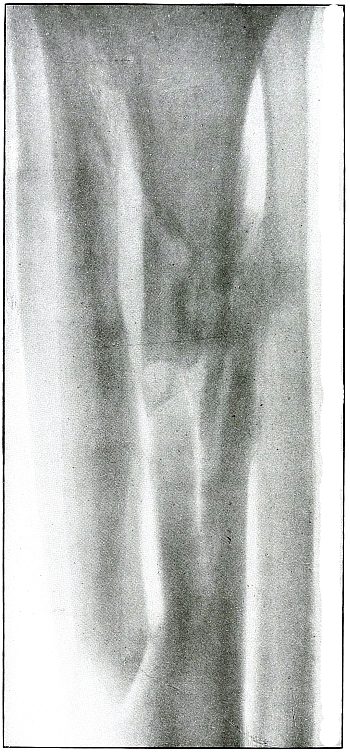

[Pg 114]

Plate 52.

[Pg 115]

Rifle—Plate 52.

LOWER EXTREMITY.

Gunshot Fracture of the Upper Shaft of the Femur.

The course of the bullet was anteroposterior and pierced the axis

of the shaft of the femur with three radiating lines of fracture,

resulting from the perforating action of the bullet striking the bone

at long range and with greatly reduced energy.

This plate shows the lateral separation of large fragments,

which is typical of gunshot wounds of long range.

Such wounds are usually not infected.

Emergency treatment is antiseptic dressing and coaptation with

extension and temporary splint, so that it may support the bone for

transportation and may be easily removable at place of continued

treatment.

In these cases with lateral separation of fragments, it is imperative

to supplement extension with pressure in a line perpendicular to the

long axis of the femur.

[Pg 116]